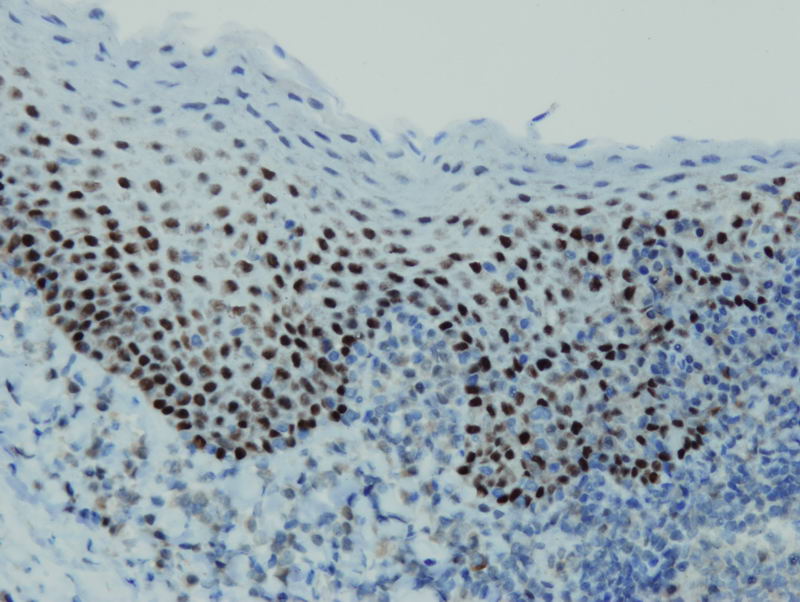

Anti-p63

Rabbit clonal antibody

Product ID:DB 134 Category:IHC-P

IHC-P, dilution 1:100

Gallery

db134a db134b db134c db134d